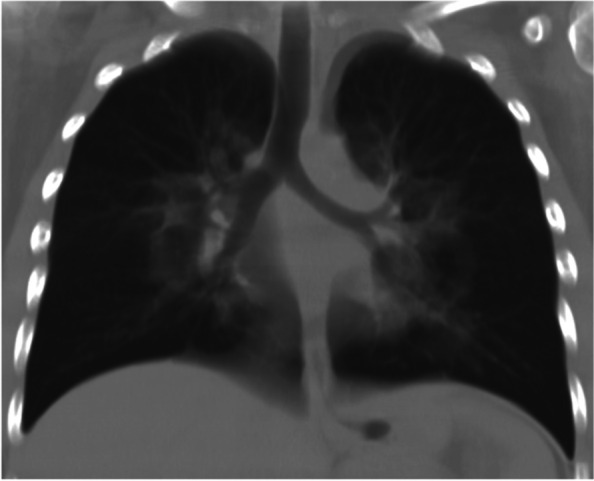

A 15-year-old Caucasian female with a history of smoking (10 cigarettes/day), multiple allergies and asthma was admitted to the Emergency Room due to respiratory failure in November 2020, following a four-days-history of dyspnoea associated with dry cough and no fever. She’d never been on treatment for her asthmatic condition due to partial improvement in adolescence and a low familiar compliance. She was started at home on amoxicillin-clavulanic acid by her general practitioner, but spontaneously decided to stop the antibiotical therapy after three days as she saw no improvement. At the admission, she presented severely dyspnoeic with a SatO2 of 75% and she was started on supplemental oxygen support at a flow rate of 3 l/min. Bilateral wheezes with prolonged expiration were present at lung auscultation. Her bloodwork showed WBC 20.000 cells/mcl (89% neutrophils) and a CRP of 0,4 mg/ml. As she was evaluated amid the COVID-19 pandemics, she underwent a first nasopharyngeal swab for SARS-CoV2 PCR (polymerase chain reaction) assessment, which turned out negative. Her chest CT (performed at another hospital, where she was first admitted) showed a central ground glass pattern with peripheral sparing (Fig. 1).

Specifically, EVALI should be suspected in a patient with a history of vaping presenting with respiratory symptoms such as shortness of breath, cough, chest pain, pleuritic chest pain and haemoptysis and/or gastrointestinal symptoms such as nausea, vomiting, diarrhoea and abdominal pain. Systemic symptoms such as fever, tachycardia and tachypnoea may be present. Hypoxemia may be present and progression to respiratory failure is common [ref. 12]. Bloodwork doesn’t show specifical evidences, nevertheless, some elements may be evocative of EVALI: a non-specific raise of the inflammation indexes may be detected. Blood exams may also be useful to exclude other processes in the differential diagnosis [ref. 13, ref. 14]. The radiological evaluation in patients with suspected EVALI generally shows diffuse hazy or consolidative opacities at the chest radiograph. Chest CT would typically show a ground glass imaging with spare of the sub pleural space [ref. 15]. GGOs (Ground-glass opacification) are common, and the most useful imaging features to help differentiate EVALI from COVID-19 are subpleural sparing of pulmonary opacities (GGOs) and centrilobular nodules (infrequent in COVID-19) (Fig. 2). In our case there was no thickening of the interlobular septa, but the reversed halo sign was present (atoll sign) (Fig. 3), which is characterized by the presence of a central ground-glass opacity surrounded by dense consolidation of crescentic shape or complete ring (sign present in late phase COVID-19 and typical of BOOP (bronchiolitis obliterans organizing pneumonia) and Wegener). These findings are consistent with diffuse alveolar damage, as seen in acute respiratory distress syndrome. The radiological findings vary according to the underlying histopathological process. Histology isn’t routinely performed, several pathologic patterns of lung injury have been reported in the setting of vaping such as lipoid pneumonia, diffuse alveolar damage, acute eosinophilic pneumonia, organizing pneumonia, diffuse alveolar haemorrhage, respiratory bronchiolitis interstitial lung disease, hypersensitivity pneumonitis and giant cell interstitial pneumonia, prompting the heterogeneity of the underlying disease processes. [ref. 16–ref. 21]. At the broncho alveolar lavage fluid (BAL) of affected patients the most commonly found substances appeared to be tetrahydrocannabinol (THC) and/or vitamin E acetate, the presence of lipid-laden macrophages seen with oil red O staining has been reported as well [ref. 22, ref. 23]. Vitamin E had been recently looked at as possible culprit in the pathogenesis of EVALI as multiple studies report its presence in the BAL samples from patients affected from EVALI, while it hasn’t been detected in healthy individuals [ref. 9, ref. 23]. Vitamin E is often used as a thickening agent of illegal THC containing vapes. According to the American public health authorities, in order to formalise the diagnosis of EVALI, vaping should be present within 90 days prior to the symptom onset, an underlying infectious cause needs to be ruled out and there should be no evidence of other plausible diagnoses (e.g. cardiac, rheumatologic or neoplastic processes) [ref. 9, ref. 24].